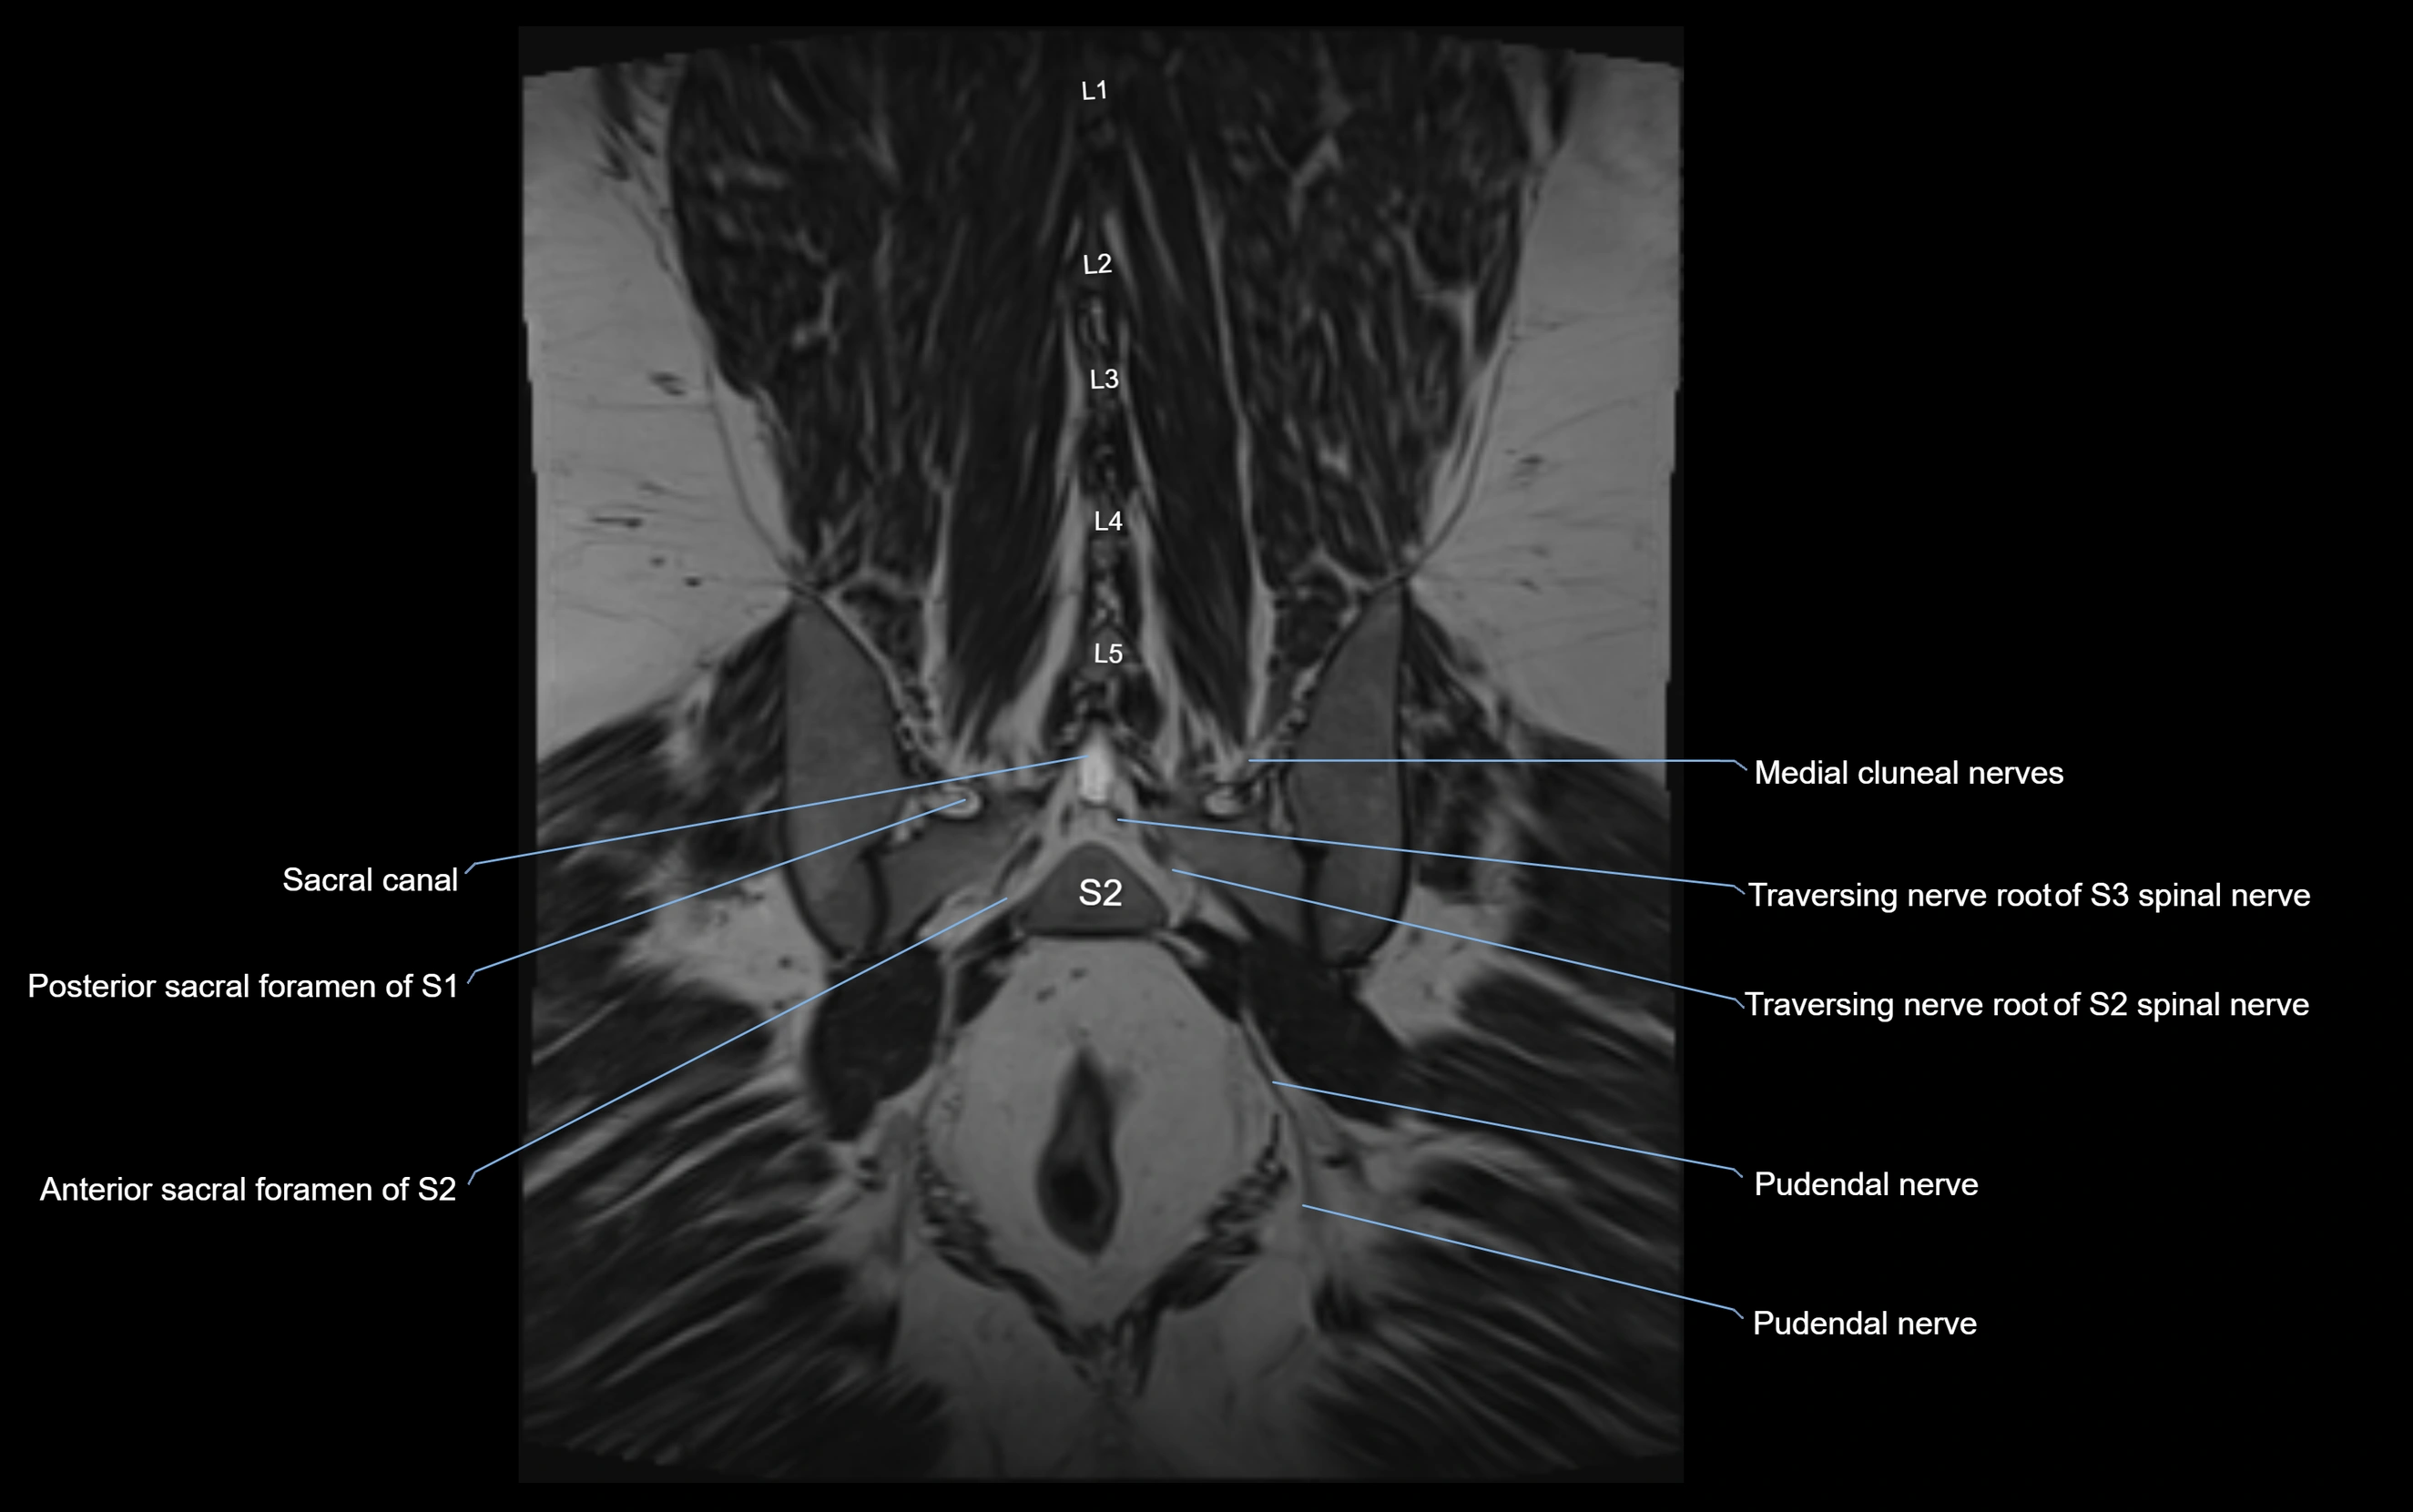

MRI Appearance

T1-weighted images:

• Nerve appears as a very thin low-to-intermediate signal intensity structure

• Surrounded by bright fat, aiding visualization

T2-weighted images:

• Nerve shows intermediate to mildly hyperintense signal compared to muscle

• Pathological involvement appears brighter

STIR (Short Tau Inversion Recovery):

• Normal nerve appears dark

• Inflamed or entrapped nerve appears bright hyperintense

T1 Fat-Sat Post-Contrast:

• Normal nerve enhances minimally

• Pathologic nerve (neuritis, entrapment, tumor infiltration) shows focal or diffuse enhancement

3D T2 SPACE / CISS:

• Nerve appears intermediate to mildly hyperintense compared to muscle

• Surrounded by bright fat or CSF, improving visualization

• Best sequence for mapping small pelvic nerves such as the anococcygeal

MRI image

image